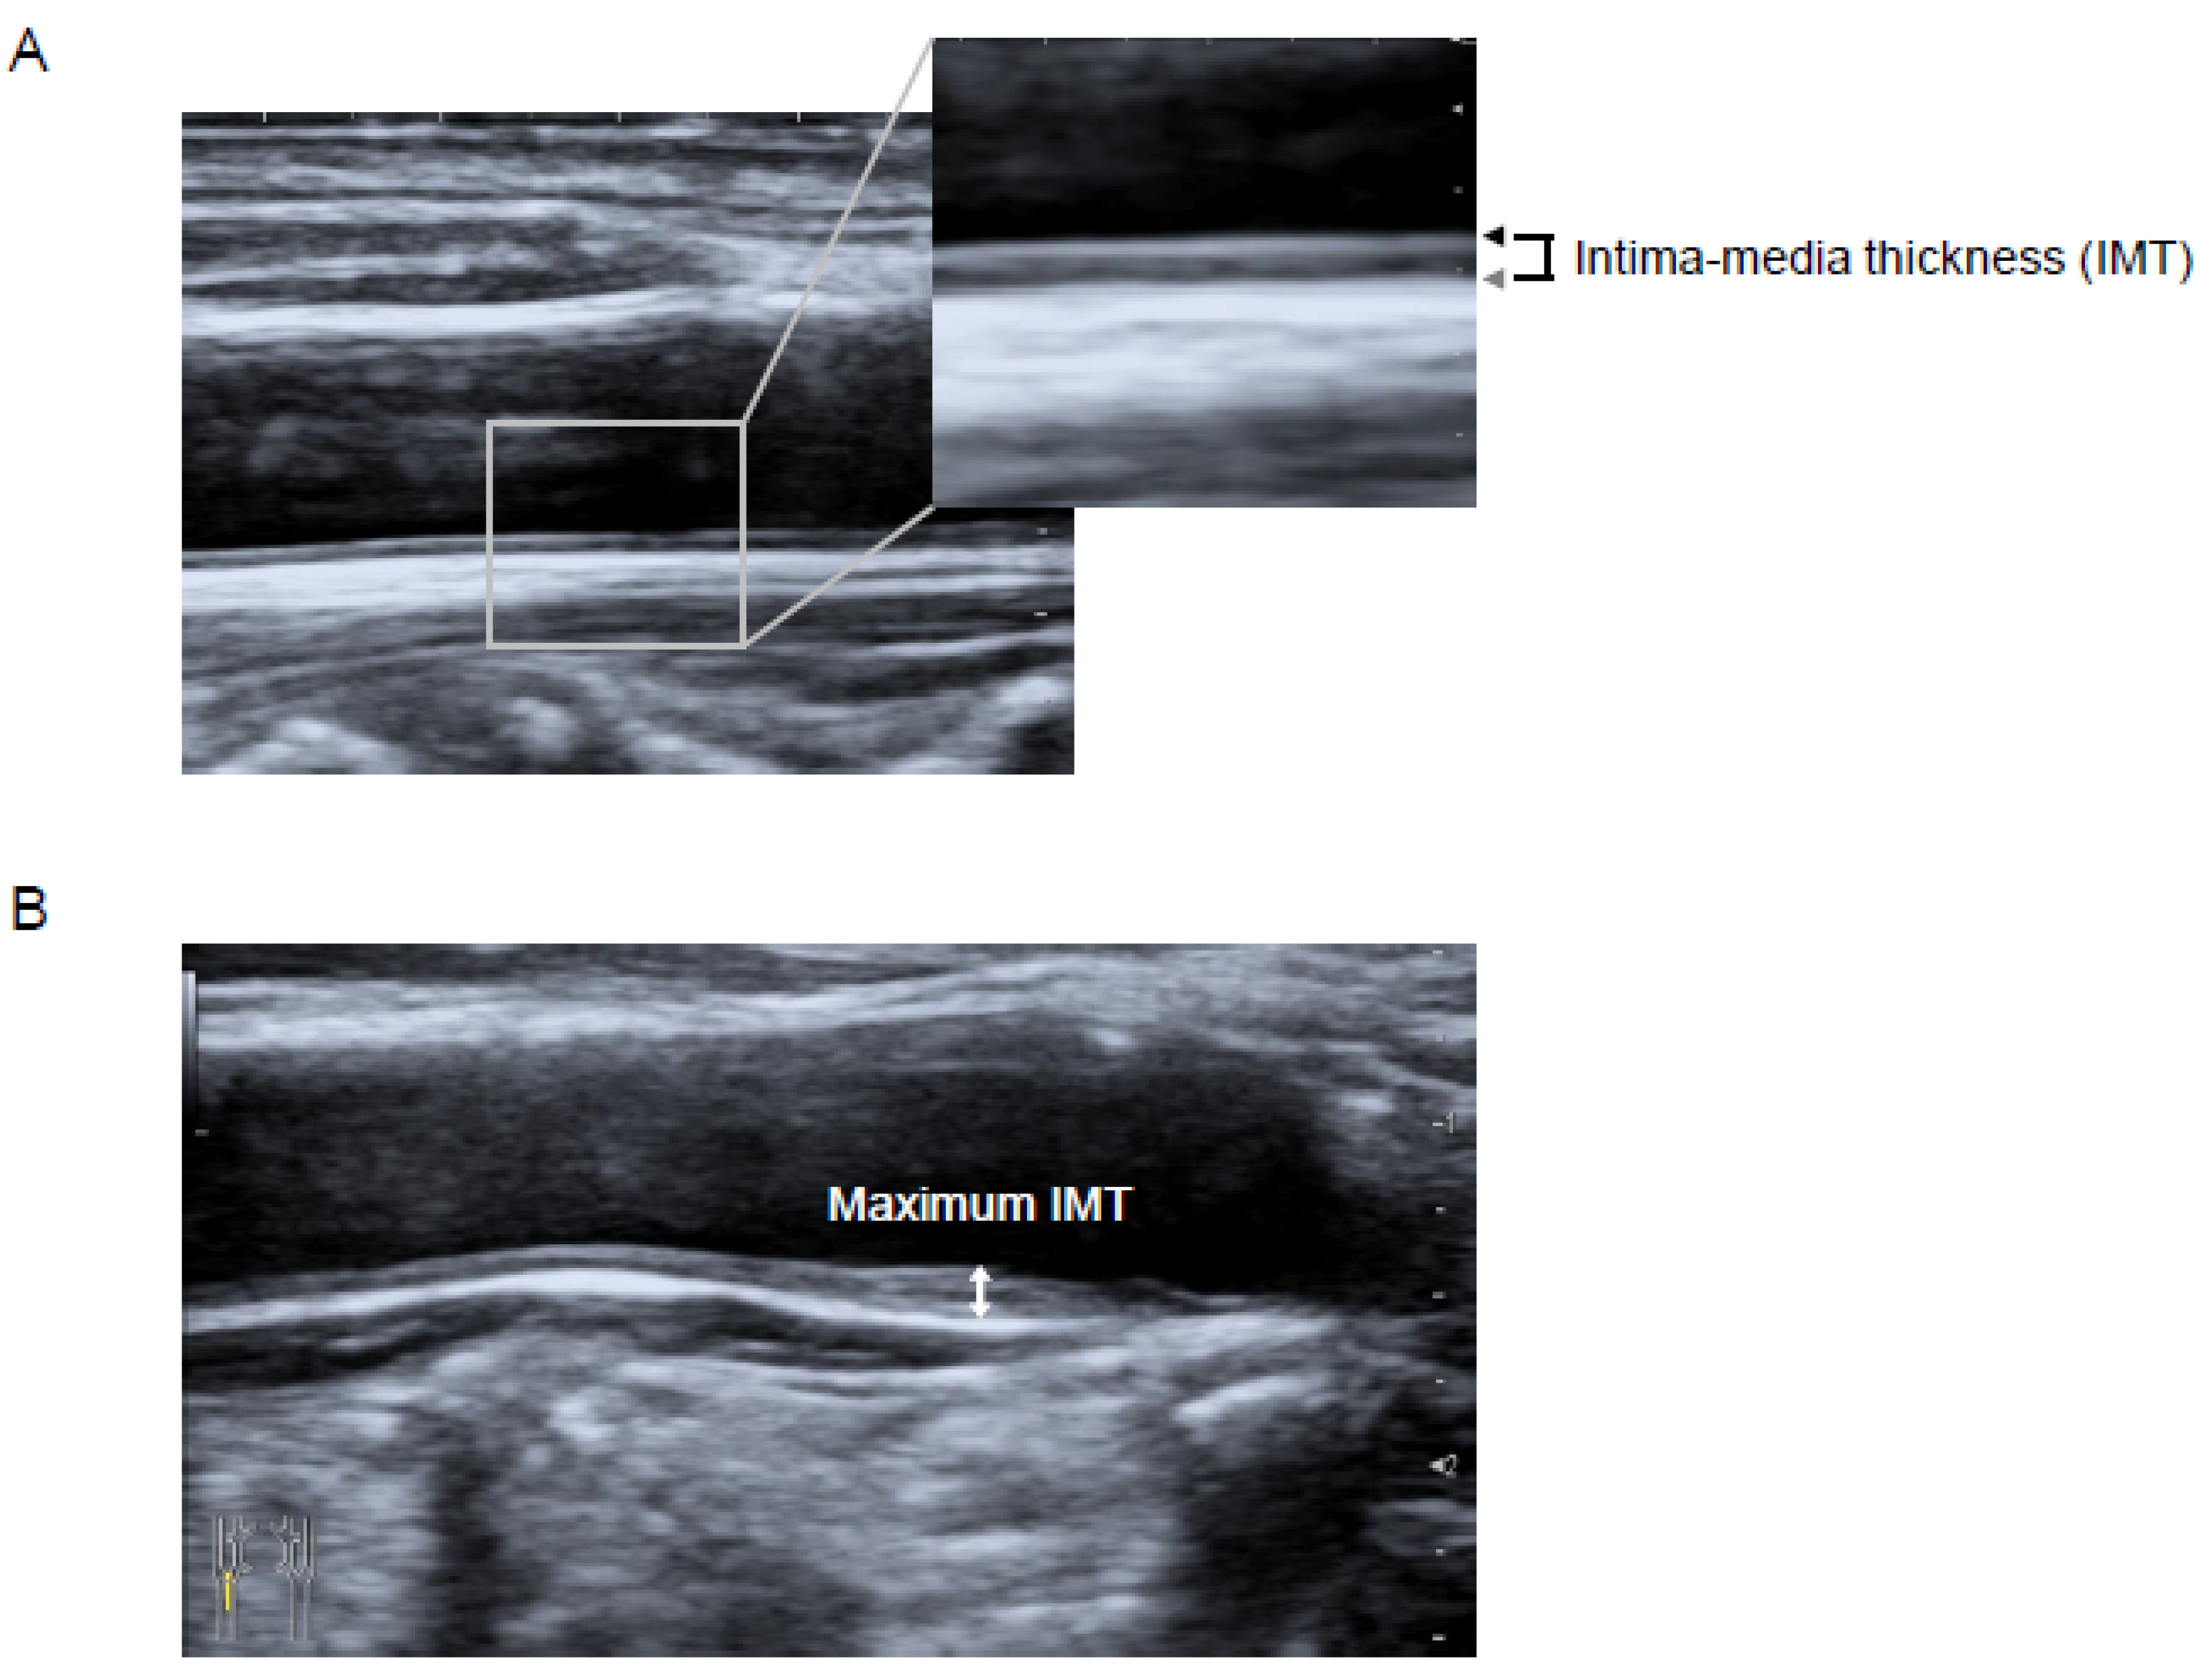

2.5. Ultrasonographic Measurement of Carotid IMT

- Pignoli, P.; Tremoli, E.; Poli, A.; Oreste, P.; Paoletti, R. Intimal plus medial thickness of the arterial wall: A direct measurement with ultrasound imaging. Circulation 1986, 74, 1399–1406. [Google Scholar] [CrossRef] [PubMed]

- Nair, S.B.; Malik, R.; Khattar, R.S. Carotid intima–media thickness: Ultrasound measurement, prognostic value and role in clinical practice. Postgrad. Med J. 2012, 88, 694–699. [Google Scholar] [CrossRef] [PubMed]